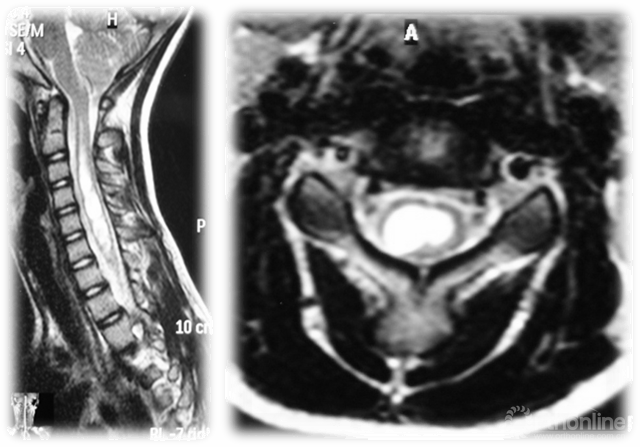

脊髓空洞

Evaluation of EOS:

● Plain X-rays are sufficient to make the diagnosis of EOS.

● MRI may be indicated for curves that are larger than 20 degrees or progressive, or if there are signs or symptoms of neurologic problems and in persistent or progressive infantile idiopathic scoliosis. Intraspinal abnormalities are commonly associated with EOS, particularly congenital scoliosis.

● CT best helps visualize bone anatomy in congenital scoliosis, and is often useful for surgical planning, but must be weighed against risk of radiation to young child.

EOS的评估:

● 普通的X线检查足以诊断EOS。

● MRI可提示超过20度的侧凸或侧凸的进展,或者有迹象或症状的神经问题,以及处在稳定或进展的幼儿特发性脊柱侧凸。脊柱的异常通常与EOS有关,特别是先天性脊柱侧凸。

● CT是最有助于使先天性脊柱侧凸的骨骼解剖得到可视化,通常也对手术方案的制定有所帮助,但必须权衡给年轻孩子带来的辐射风险。